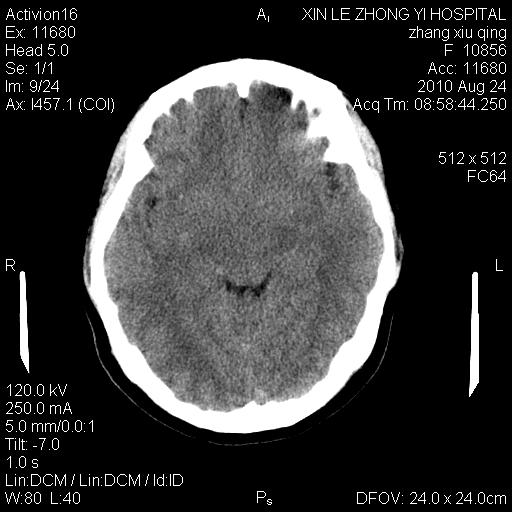

标题: CT28569:看看鞍上池正常吗 [打印本页]

标题: CT28569:看看鞍上池正常吗

女 24 偶有头晕

未见明显异常,必要时可作mri

没什么!只是扫描层面与听眦线不平行

未见异常